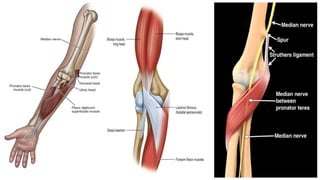

PRONATOR SYNDROME

It is a compression of median nerve between the two heads of pronator muscle at the level of

The potential sites of entrapment include:

• Fibrous bands between ulnar and humeral heads of PT where the median nerve passes most

common cause of compression.

• Thickened or tight bicipital aponeurosis (lacertus fibrosus)

• Supracondylar process: Present in 1% of population. It is a residual osseous structure on

distal humerus that gives rise to ligament of Struthers (this structure is different from arcade of

Struthers which is a site of ulnar compression neuropathy in cubital tunnel syndrome). The ligament

travels from tip of supracondylar process to medial epicondyle. The site is a rare point for

compression.

• Flexor digitorum superficialis (FDS) aponeurotic arch